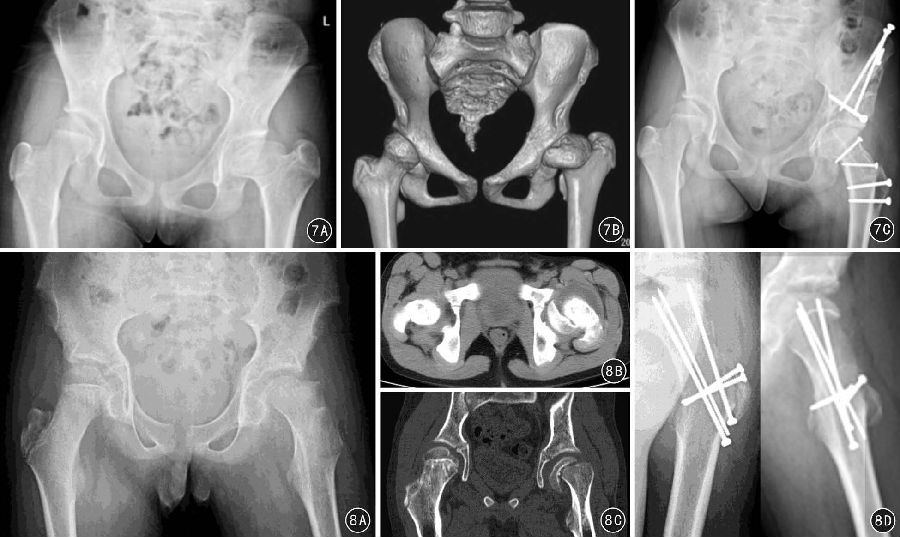

3.6 股骨头颈部严重畸形的处理

对股骨头颈部严重畸形,如股骨头骨骺滑脱、大头畸形等病变,在深入研究股骨头血液供应的临床解剖基础上,Ganz 等在SHD的基础上进一步推出了股骨颈软组织瓣延长技术(图6)。为处理股骨头复杂情况,研究者又开展了股骨头缩小成型术(图7)、股骨颈相对延长术(图7)、股骨头骨骺滑脱复位术(图8)等技术。股骨颈软组织瓣延长技术的手术操作要点是:在SHD 基础上,对大转子后侧突出部分的骨质进行骨膜内剥离、摘除,将股骨颈骨膜连同大转子后方的软组织瓣一同充分游离和松解,避免在对股骨头进行操作时MFCA 过度牵拉造成股骨头缺血。然后在矢状面对股骨头缩小截骨成形、在股骨头颈交界处进行股骨头的内翻/ 外翻截骨以及对严重股骨头骨骺滑脱进行复位,避免继发撞击征和髋骨关节炎形成。

图8 患者男,25岁,颅咽管瘤术后8年,左侧股骨头骨骺滑脱3个月余, 经髋关节外科脱位手术入路行股骨头滑脱复位内固定术,8A 术前骨盆正位X线片,8B 术前螺旋CT检查显示左股骨头骨骺向后内侧严重滑脱,8C 术前螺旋CT冠状位重建检查显示左股骨头骨骺向内下方严重滑脱,8D 术后3个月左髋关节正、斜位X 线片显示复位固定良好,无股骨头坏死